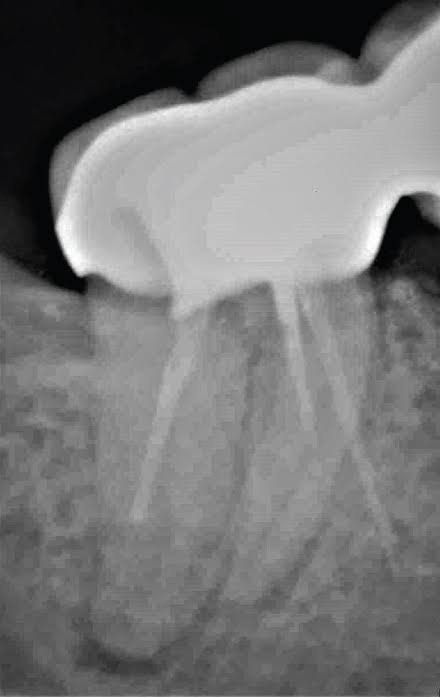

3. What Condition can be seen in this X ray regarding the tooth # 2.2?